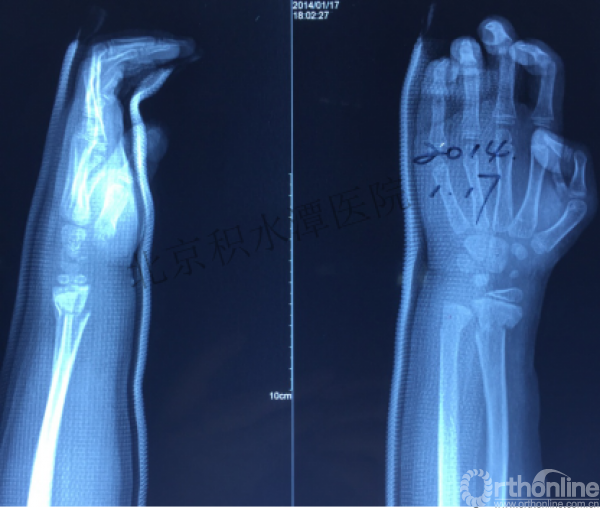

病例分享六

7岁、男孩,桡骨远端骨折

原始损伤片

手法整复后 - 45分钟!

伤后4天复查

伤后30天!

医生的处理方法!——医生终于没有坚持自己的原则!

伤后40天—切开复位内固定!

伤后18个月

如何面对?

心情之压抑无以言表!

手术历时近 5小时!心情之压抑无以言表!因为当时的经治医生是他们的进修生!感觉是他们的失职甚至渎职!

唯一可以肯定—预后不佳!郭教授是党员!是无神论者!但是很诡异的事情:手术中发生—C形臂看不清!拍片条件总是调节不好!手术器械换了三套!内固定钢板总不合适!

术后15月,虽然家长满意了,但是他们医生不满意!